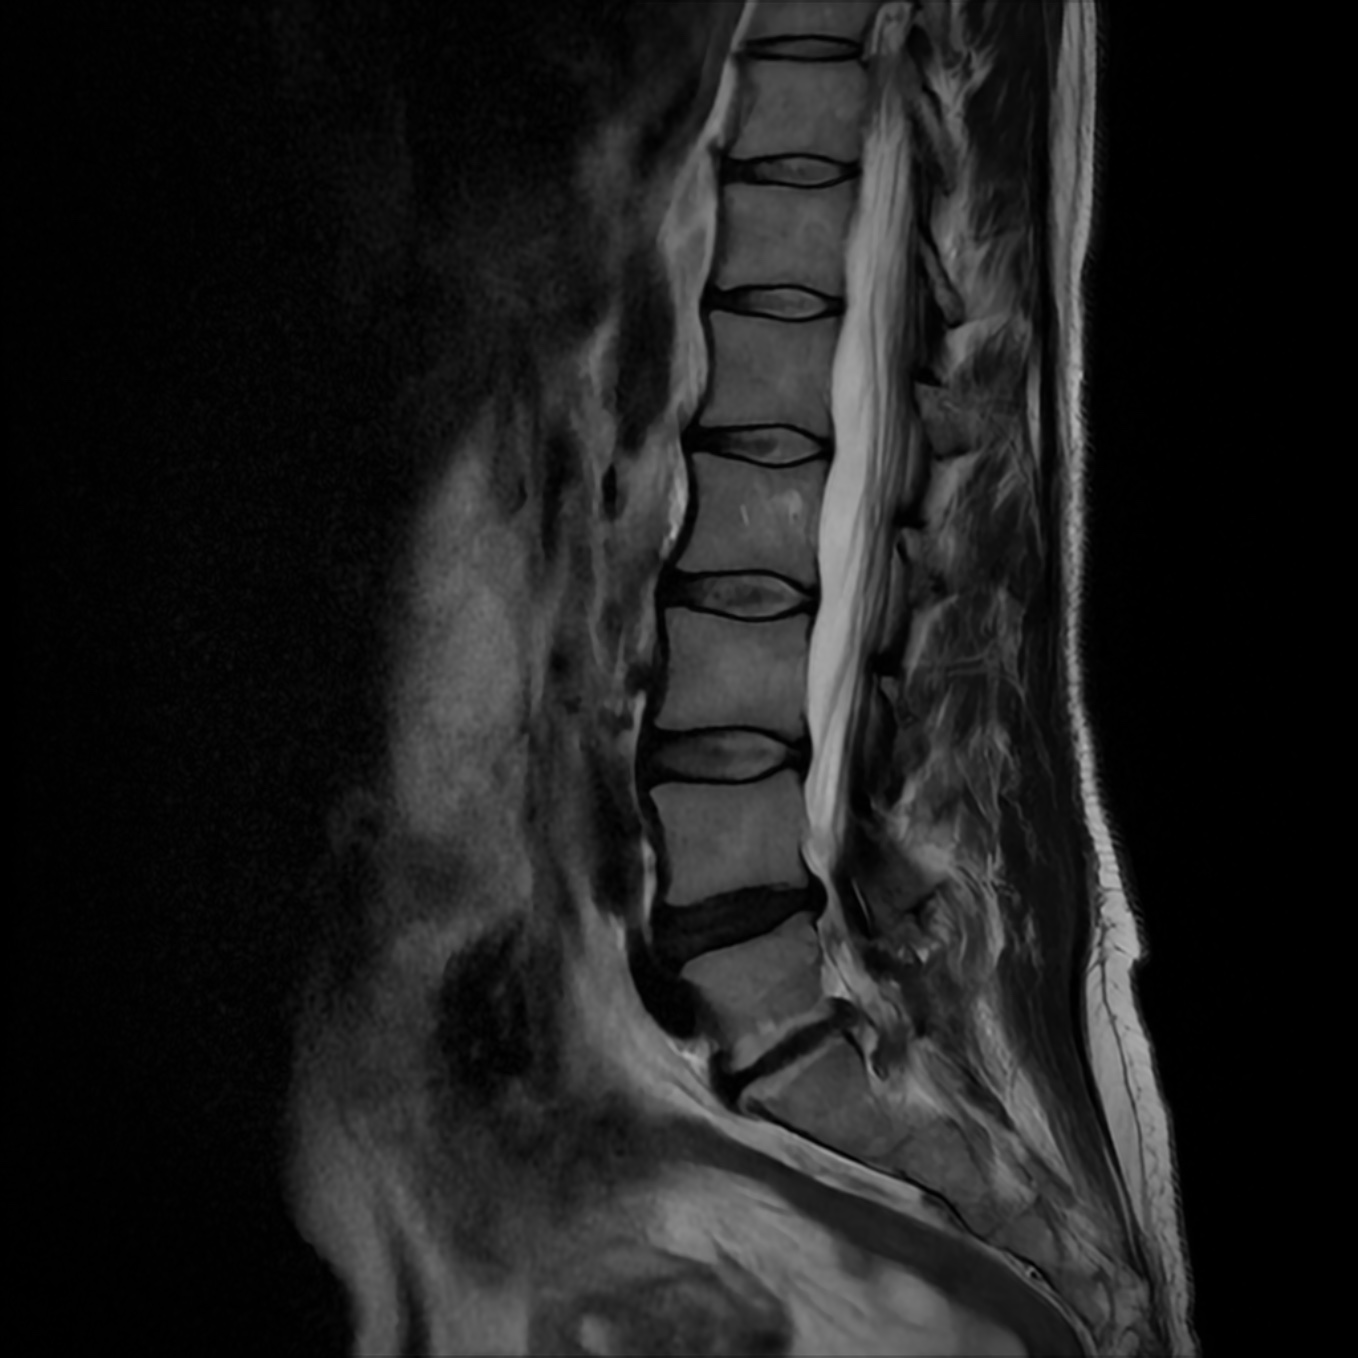

2. Zmiany zwyrodnieniowe kręgosłupa

Z wiekiem nasze kręgosłupy ulegają naturalnym procesom degeneracyjnym. Zmniejszenie aktywności fizycznej i osłabienie mięśni stabilizujących kręgosłup mogą prowadzić do przeciążeń kręgów i tkanek kręgosłupa, co skutkuje bólami o charakterze stałym lub przerywanym, nasilającymi się podczas ruchu lub długotrwałego stania.